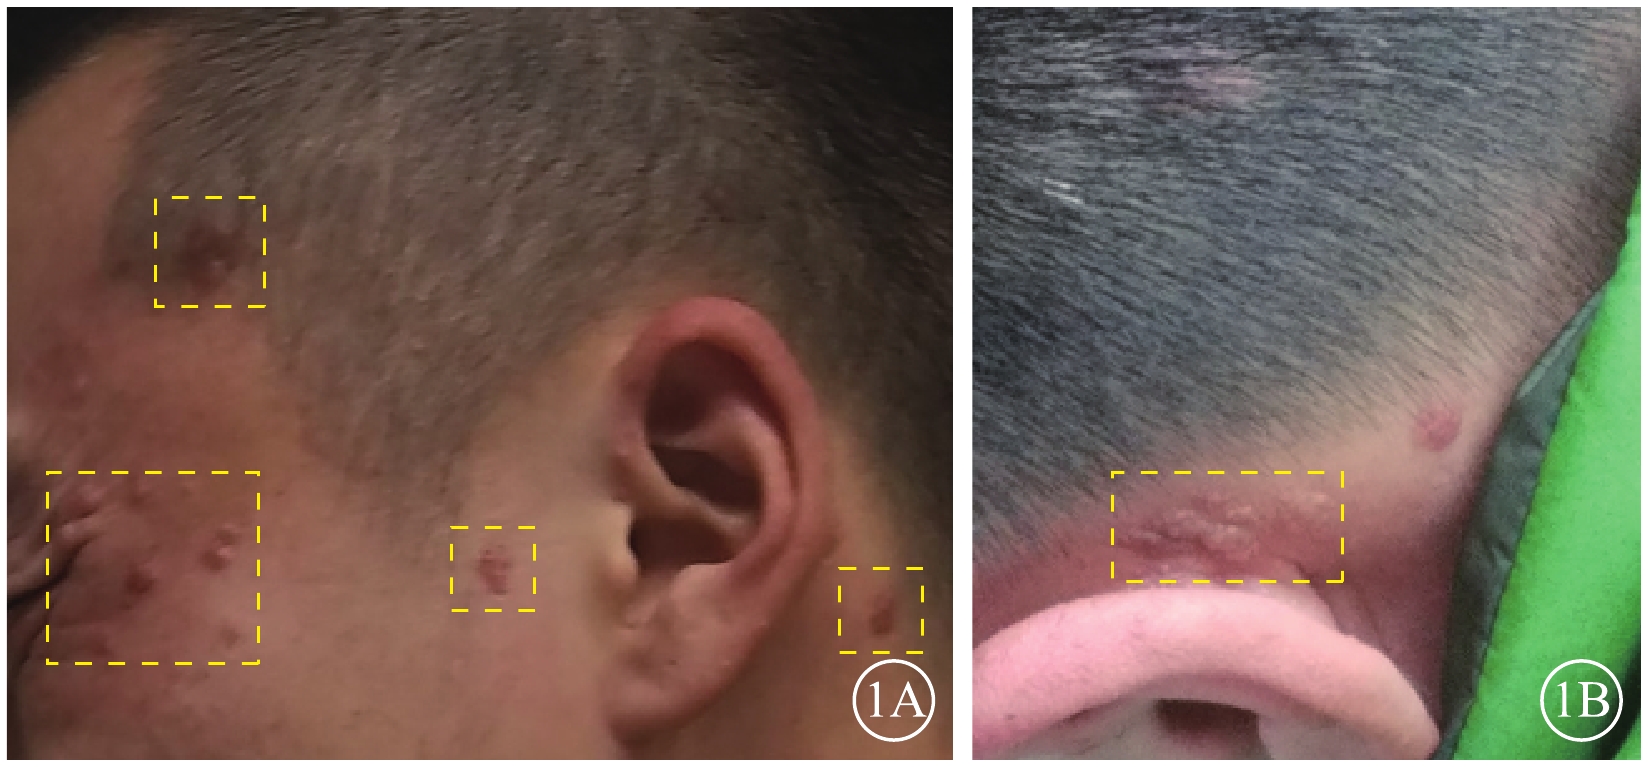

眼部檢查:右眼裸眼視力0.8,矯正視力1.0;左眼裸眼視力0.15,矯正不能提高。雙眼眼壓及眼前節檢查正常。眼底檢查,左眼視盤下方可見大小約1/2個視盤直徑(DD)的局限性黃白色隆起病灶,其周圍滲出性視網膜脫離。右眼眼底無異常。外院熒光素眼底血管造影(FFA)檢查,左眼早期視盤顳下方約1 DD大小的橢圓形弱熒光,周圍環繞不均勻強熒光,黃斑區廣泛彌漫弱熒光,視盤上方兩處1/4 DD大小、顳上血管弓處兩處1/2 DD大小橢圓形稍強熒光(圖2A);晚期各病灶熒光素滲漏明顯,邊界不清(圖2B)。右眼上方血管弓處1/2 DD大小病灶早期稍強熒光,晚期熒光素滲漏(圖2C)。吲哚青綠血管造影(ICGA)檢查,左眼早期視盤顳下弱熒光,周邊環繞強熒光環(圖2D);晚期病灶周圍熒光素滲漏,邊界不清(圖2E),其余FFA檢查可見的病灶在ICGA上未見明顯異常熒光。右眼早晚期均可見上方血管弓處片狀弱熒光(圖2F)。

圖2

患者雙眼眼底血管造影像。2A. 左眼FFA早期,視盤顳下方約1 DD大小橢圓形弱熒光,周圍環繞不均勻強熒光(紅箭);2B. 左眼FFA晚期,視盤上方兩處1/4 DD大小病灶熒光素滲漏明顯(黃箭),視盤下方病灶熒光素滲漏邊界不清(紅箭);2C. 右眼FFA晚期,上方血管弓處可見熒光素滲漏(黃箭);2D. 左眼ICGA早期,視盤顳下早期弱熒光病灶,周邊繞以強熒光環(紅箭);2E. 左眼ICGA晚期,視盤下方病灶周圍熒光素滲漏,邊界不清(紅箭),黃斑區強弱熒光混雜(綠箭);2F. 右眼ICGA晚期,上方血管弓處片狀弱熒光(黃箭)

圖2

患者雙眼眼底血管造影像。2A. 左眼FFA早期,視盤顳下方約1 DD大小橢圓形弱熒光,周圍環繞不均勻強熒光(紅箭);2B. 左眼FFA晚期,視盤上方兩處1/4 DD大小病灶熒光素滲漏明顯(黃箭),視盤下方病灶熒光素滲漏邊界不清(紅箭);2C. 右眼FFA晚期,上方血管弓處可見熒光素滲漏(黃箭);2D. 左眼ICGA早期,視盤顳下早期弱熒光病灶,周邊繞以強熒光環(紅箭);2E. 左眼ICGA晚期,視盤下方病灶周圍熒光素滲漏,邊界不清(紅箭),黃斑區強弱熒光混雜(綠箭);2F. 右眼ICGA晚期,上方血管弓處片狀弱熒光(黃箭)

眼部檢查:右眼裸眼視力0.8,矯正視力1.0;左眼裸眼視力0.15,矯正不能提高。雙眼眼壓及眼前節檢查正常。眼底檢查,左眼視盤下方可見大小約1/2個視盤直徑(DD)的局限性黃白色隆起病灶,其周圍滲出性視網膜脫離。右眼眼底無異常。外院熒光素眼底血管造影(FFA)檢查,左眼早期視盤顳下方約1 DD大小的橢圓形弱熒光,周圍環繞不均勻強熒光,黃斑區廣泛彌漫弱熒光,視盤上方兩處1/4 DD大小、顳上血管弓處兩處1/2 DD大小橢圓形稍強熒光(圖2A);晚期各病灶熒光素滲漏明顯,邊界不清(圖2B)。右眼上方血管弓處1/2 DD大小病灶早期稍強熒光,晚期熒光素滲漏(圖2C)。吲哚青綠血管造影(ICGA)檢查,左眼早期視盤顳下弱熒光,周邊環繞強熒光環(圖2D);晚期病灶周圍熒光素滲漏,邊界不清(圖2E),其余FFA檢查可見的病灶在ICGA上未見明顯異常熒光。右眼早晚期均可見上方血管弓處片狀弱熒光(圖2F)。

圖2

患者雙眼眼底血管造影像。2A. 左眼FFA早期,視盤顳下方約1 DD大小橢圓形弱熒光,周圍環繞不均勻強熒光(紅箭);2B. 左眼FFA晚期,視盤上方兩處1/4 DD大小病灶熒光素滲漏明顯(黃箭),視盤下方病灶熒光素滲漏邊界不清(紅箭);2C. 右眼FFA晚期,上方血管弓處可見熒光素滲漏(黃箭);2D. 左眼ICGA早期,視盤顳下早期弱熒光病灶,周邊繞以強熒光環(紅箭);2E. 左眼ICGA晚期,視盤下方病灶周圍熒光素滲漏,邊界不清(紅箭),黃斑區強弱熒光混雜(綠箭);2F. 右眼ICGA晚期,上方血管弓處片狀弱熒光(黃箭)

圖2

患者雙眼眼底血管造影像。2A. 左眼FFA早期,視盤顳下方約1 DD大小橢圓形弱熒光,周圍環繞不均勻強熒光(紅箭);2B. 左眼FFA晚期,視盤上方兩處1/4 DD大小病灶熒光素滲漏明顯(黃箭),視盤下方病灶熒光素滲漏邊界不清(紅箭);2C. 右眼FFA晚期,上方血管弓處可見熒光素滲漏(黃箭);2D. 左眼ICGA早期,視盤顳下早期弱熒光病灶,周邊繞以強熒光環(紅箭);2E. 左眼ICGA晚期,視盤下方病灶周圍熒光素滲漏,邊界不清(紅箭),黃斑區強弱熒光混雜(綠箭);2F. 右眼ICGA晚期,上方血管弓處片狀弱熒光(黃箭)